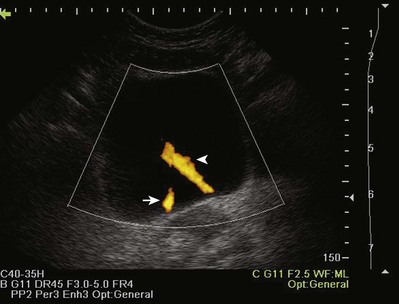

Color Doppler ultrasonography allows for evaluation of the velocity and direction of motion. A color map may be applied to direction with the most common assignation of the color blue to motion away from the transducer and red for motion toward the transducer. The velocity of motion is designated by the intensity of the color; thus the brighter the color is, the more rapid the motion. Color Doppler may be used to evaluate the presence of absence of blood flow in the kidney, testes, penis, and prostate. It also may be useful in the detection of ureteral “jets” of urine emerging from the ureteral orifices.